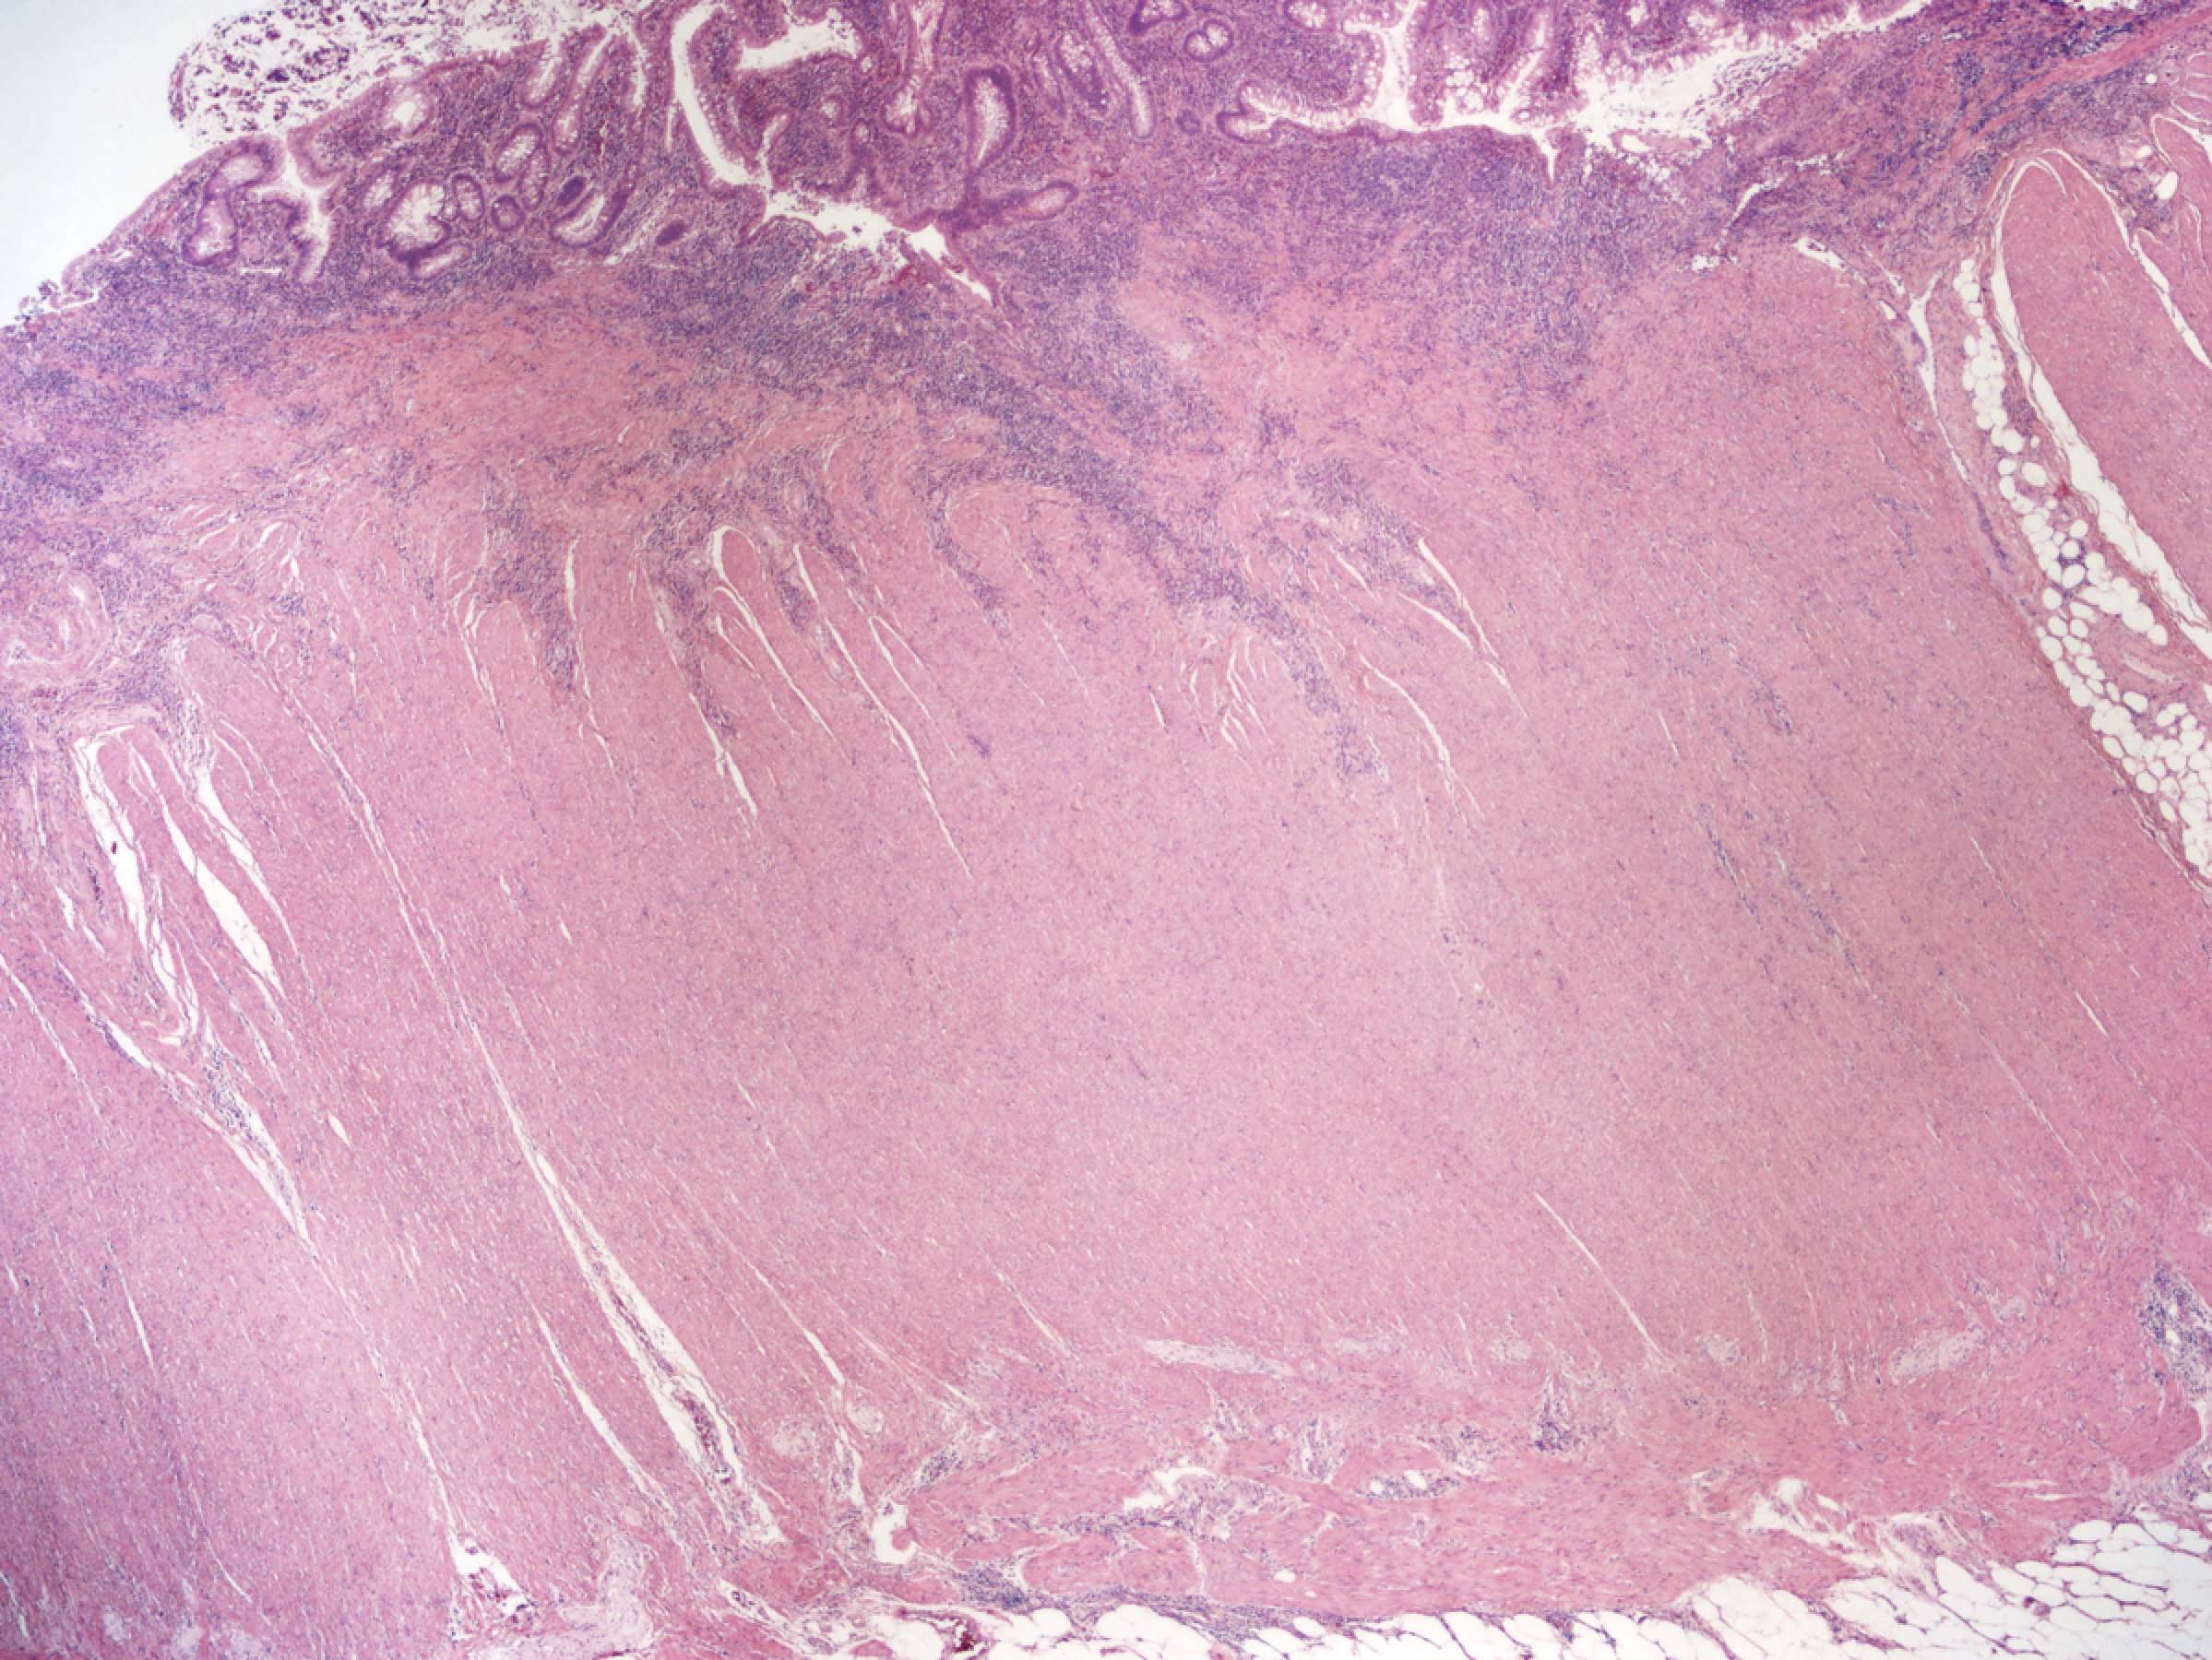

A 26 year old woman with no significant past medical history is found to have severe colitis and undergoes total abdominal colectomy. The gross examination of the resection specimen reveals a predominantly left sided colitis with discontinuous involvement of the cecal and periappendiceal mucosa, as shown in the image above. Microscopic evaluation demonstrates a mucosa based, active chronic colitis without evidence of transmural inflammation. Several nonnecrotizing epithelioid cell granuloma associated with ruptured crypts are identified. Which of the following is true regarding the patient’s pathologic diagnosis?

The photograph shows a total abdominal colectomy specimen with a predominantly left sided colitis and discontinuous involvement of the cecal or periappendiceal mucosa. The gross and microscopic findings are convincing for a diagnosis of ulcerative colitis. It is well documented that patients with left sided ulcerative colitis may have discontinuous involvement of the periappendiceal or cecal mucosa, known as a cecal patch. A diagnosis of IBD, indeterminate type should be avoided when dealing with well recognized variants of IBD, such as ulcerative colitis with cecal patch and superficial (ulcerative colitis-like) Crohn's disease. Nonnecrotizing epithelioid cell granulomas associated with ruptured crypts (cryptolytic granulomas) are known to occur in cases of ulcerative colitis and often result in diagnostic difficulties; however, this finding should not preclude a diagnosis of ulcerative colitis.